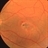

- RETINAL HOLE

- retinal hole, argon photocoagulation, choroidal neovascular membrane (CNVM), laser photocoagulation, complication

Fundus camera

Topcon VT-50 - Description

- 63-year-old patient with retinal (macular) hole s/p laser photocoagulation for CNVM OS; VA= counting fingers at 6 feet.